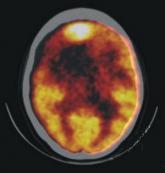

腦缺血見于多種神經外科疾病的病理過程中,如腦血管病、腦腫瘤等,也可見于心臟驟停、休克等全身性病理過程。腦缺血可表現為不同形式,有局灶性和彌漫性腦缺血、永久性和暫時性腦缺血之分。但不論以何種方式出現,腦缺血的病理生理機制和生化改變基本相似,且與腦缺血的程度和持續時間相關。